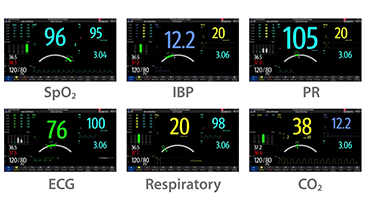

Resona 7, ĂŒstĂŒn dĂŒzeyde g?rĂŒntĂŒ kalitesine ek olarak, vaskĂŒler hemodinamik de?erlendirmesi i?in devrim niteli?indeki V Ak??? ile fetĂŒs CNS tan?lamas? i?in 3 boyutlu veri kĂŒmesinden dĂŒzlem g?rĂŒntĂŒsĂŒ alma konusunda en iyi birime sahip oldu?undan, klinik ara?t?rma yeterliklerini de art?rmaktad?r. En sezgisel, harekete dayal? ?oklu dokunmatik i?letim ile tĂŒm temel klinik ?zellikleri bir araya getiren Resona 7, ultrason yenili?i konusunda ger?ek anlamda yeni dalgalara ?ncĂŒlĂŒk ediyor.